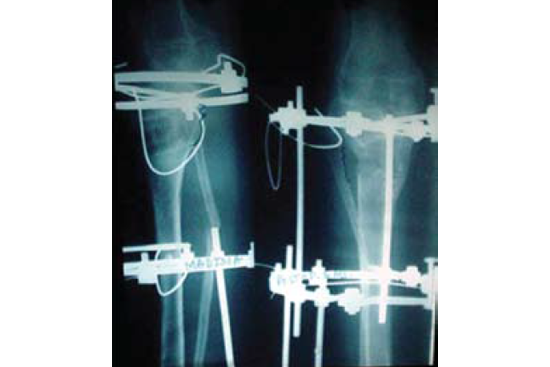

Knee Deformity